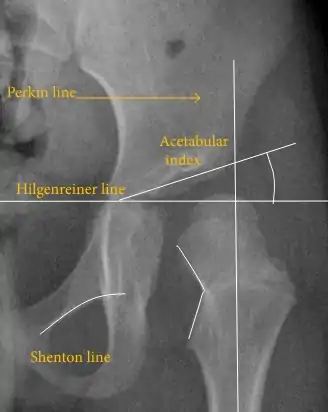

Despite the widespread use of ultrasound, pelvis X-ray is still frequently used to diagnose or monitor hip dysplasia or for assessing other congenital conditions or bone tumors.[45]

The most useful lines and angles that can be drawn in the pediatric pelvis assessing hip dysplasia are as follows:[45] Different measurements are used in adults.[45]